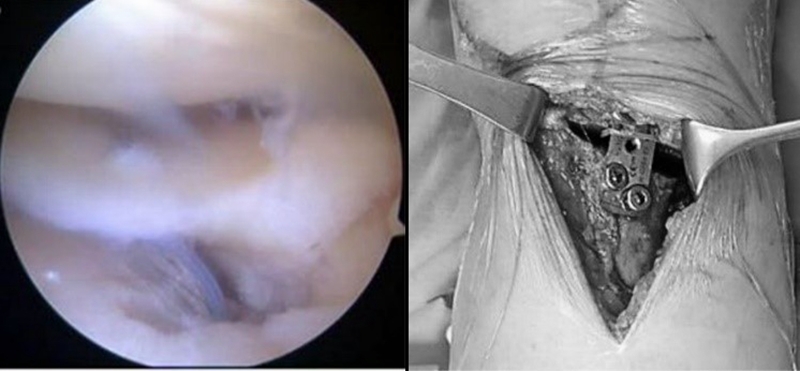

José等人采用内侧半月板后根修复联合OWHTO治疗内侧半月板后根部撕裂。他们认为在截骨术中松解内侧副韧带有利于内侧关节间隙的打开和修复半月板根部的操作,同时内侧间室减压有利于根部愈合,保证术后更快的恢复[2]。

图2